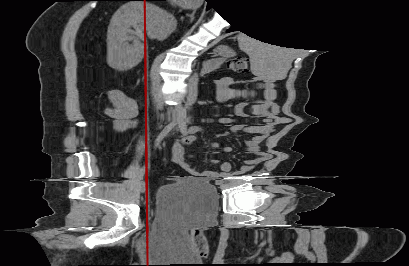

By the color of the curve, you can determine which part of the curve is located in front of the current image in space. This part of the curve is brighter than the part behind the image.

In Fig. 5.14, the central part and the third point are a brighter color. This means they are located in front of the current section.

To make it easier to find a node on the curve on all the projections, locate the cursor on this node. The node will be magnified on all the projections.